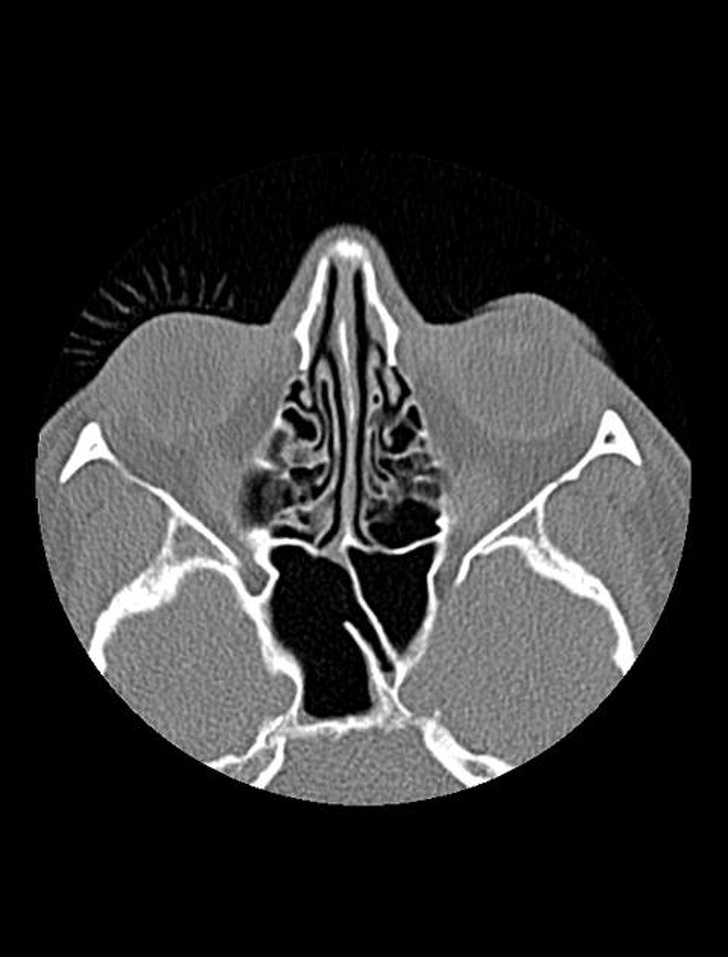

7. Жінка зробила яскравий макіяж перед процедурою КТ. Апарат відсканував нафарбовані вії